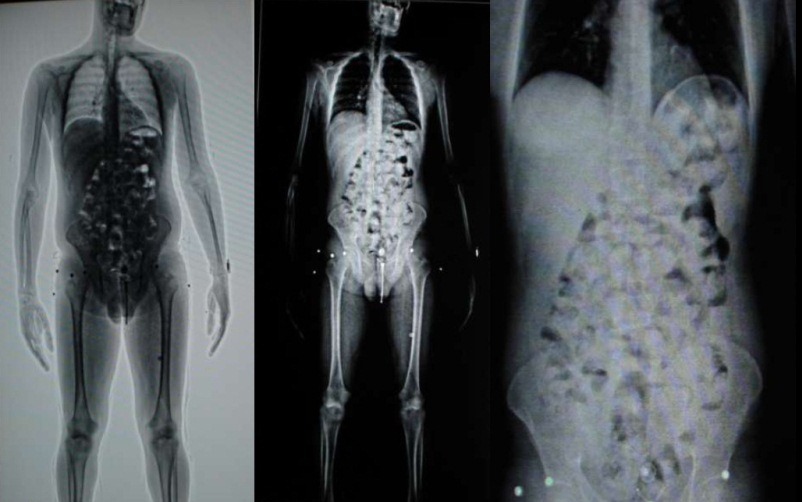

O homem, de 32 anos, foi identificado pela Polícia Federal com a droga dentro do organismo com o auxílio do equipamento Body Scan do aeroporto, que identifica se a pessoa possui algum produto dentro do corpo. O equipamento começou a funcionar na quarta.